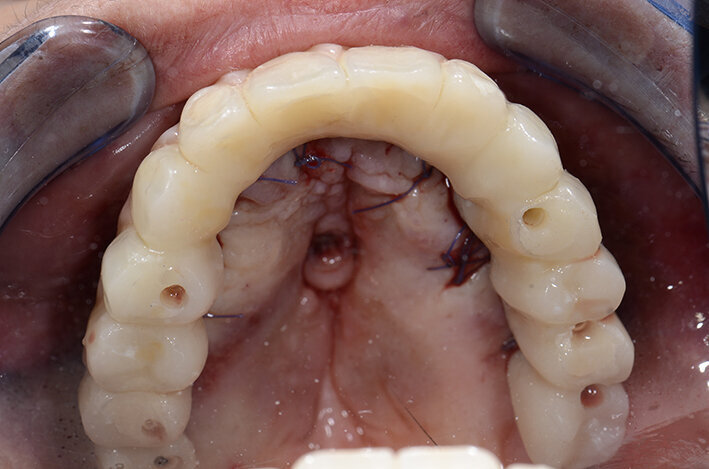

Stabilita la tecnica rigenerativa è necessario fare delle valutazioni sul periodo post operatorio e quindi sul tipo di protesi provvisoria da far indossare alla paziente. Escludendo tutte le tipologie di protesi mobili per almeno sei mesi (compresa quindi una protesi sostenuta da un impianto posizionato nel palato), sempre con l’ausilio del software di chirurgia guidata ho quindi ipotizzato l’inserimento di due impianti nella zona della tuberosità (Fig. 5). Con l’ausilio della dima chirurgica sono stati inseriti tre impianti, due nelle tuberosità mascellari e uno nel palato (Fig. 6). Sui tre impianti è stato progettato insieme ai tecnici un dispositivo in metallo che potesse sostenere dei denti fissi non rimovibili (Fig. 7). Il risultato ottenuto è stato eccellente perché la paziente ha portato una protesi fissa fin dal giorno dell’intervento per tutto il periodo di guarigione, di circa nove mesi. La progettazione della ricostruzione ossea è stata quindi fatta in maniera Protesicamente Guidata, sono stati posizionati gli impianti virtuali e poi valutata l’entità della rigenerazione necessaria.

Grazie al flusso digitale, possiamo inserie nel software anche il file STL del provvisorio pre-chirurgico preparato e quindi progettare il provvisorio immediato (Fig. 41). La pianificazione degli impianti a questo punto viene effettuata in modo protesicamente guidato ed è facile posizionare correttamente l’impianto e verificarlo nelle cross del software. Si progetta e si disegna quindi la dima chirurgica (Fig. 42). Il giorno dell’intervento abbiamo già tutto pronto e la paziente presenta uno stato di salute dei tessuti ottimale grazie anche al fatto che ha potuto portare per tutto il periodo una protesi fissa.

Procediamo quindi all’inserimento di sei impianti BLX Straumann (Straumann Group) (Fig. 43, 44), ed utilizziamo gli impianti posizionati nella tuberosità per stabilizzare la dima chirurgica e il provvisorio sul modello master di lavoro digitale. La funzionalizzazione del provvisorio immediato subito dopo l’intervento viene effettuata con l’utilizzo della tecnica DIL19 (Figg. 45, 46).